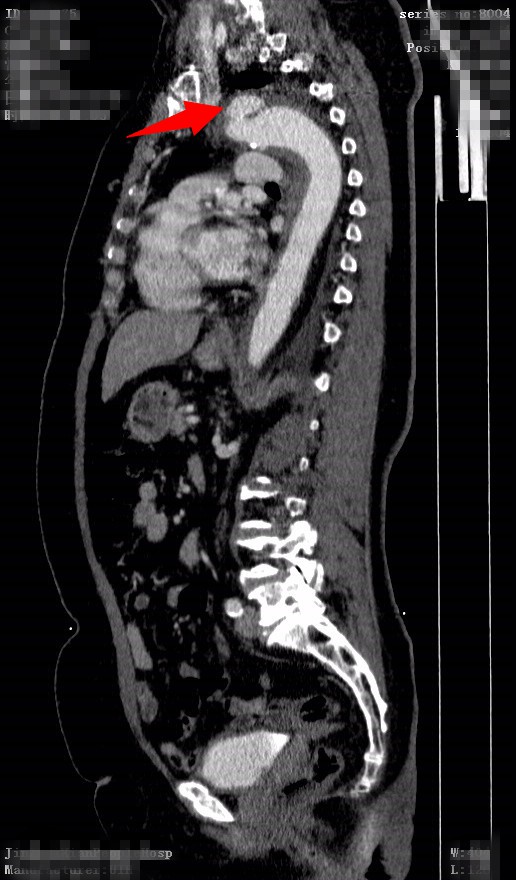

患者王某某,女性,66岁,无明显诱因下出现胸腹部不适,几日后患者自觉疼痛加重,起初未予重视,后疼痛无明显好转,来我院就诊。查胸部CT示:1、左心室增大。2、主动脉增宽,附壁血栓?主动脉夹层待排,建议CTA检查。3、双侧胸腔少量积液。胸腹部主动脉增强CT示:1、主动脉夹层。2、双下肺炎症。3、左侧胸腔积液。4、左心室增大,考虑高心病。入我院外周介入科拟"1.主动脉夹层;2.高血压病2级(极高危组);3.冠心病"收治入院。

入院后给予稳定血压、镇痛等对症治疗。近日,在全麻下行“左上肢动脉、主动脉造影+右股动脉切开+胸主动脉夹层覆膜支架腔内隔绝术”术前主动脉造影示:主动脉大弯侧见龛影,距左锁骨下动脉开口约1cm术后行主动脉造影示:主动脉弓大弯侧龛影消失,左锁骨下动脉显示良好,支架周围未见内瘘。患者术后十天复查支架位置良好。